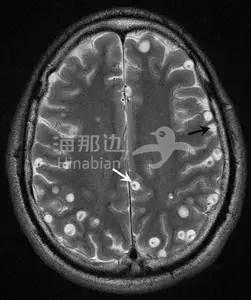

寄生虫会在人身体内“打洞”,啃噬人体组织,一旦入侵大脑,危害尤为严重。

于是他找了寄生虫方面的专家,经过检查,才知道自己感染的是曼氏迭宫绦虫。这种虫子,可以在皮下游走。

男孩全身都是正常的,直到打开颅腔,法医才发现了满脑的虫子!而这些虫子,不是蛔虫,而是猪肉绦虫的囊尾蚴。

到了脑组织发育产卵后,会压迫脑组织,引起组织炎症,危及生命。